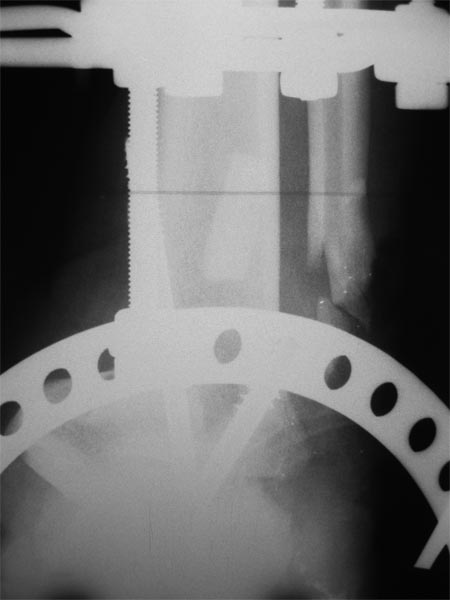

Уважаемые коллеги! Как и обещал представляю результат лечения пациента с дробовым

ранением,который обсуждался в теме http://weborto.net/forum/1350149570/index_html.

Фото содержатся во вложенном файле. Пациенту для закрытия дефекта выполнена резекция

таранной кости, пяточно-большебецовый артродез винтами. После укорочения сформировался

запас тканей, достаточный для закрытия дефекта. Далее несколько дней повязка с низким

давлением и свободная аутодермопластика. Пациент выписан. После окончательного

заживления планируем демонтировать аппарат и перейти на циркулярную повязку. Когда по

Вашему мнению следует давать нагрузку?